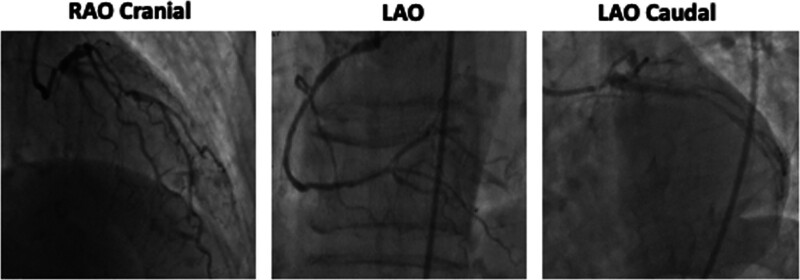

Abstract Image